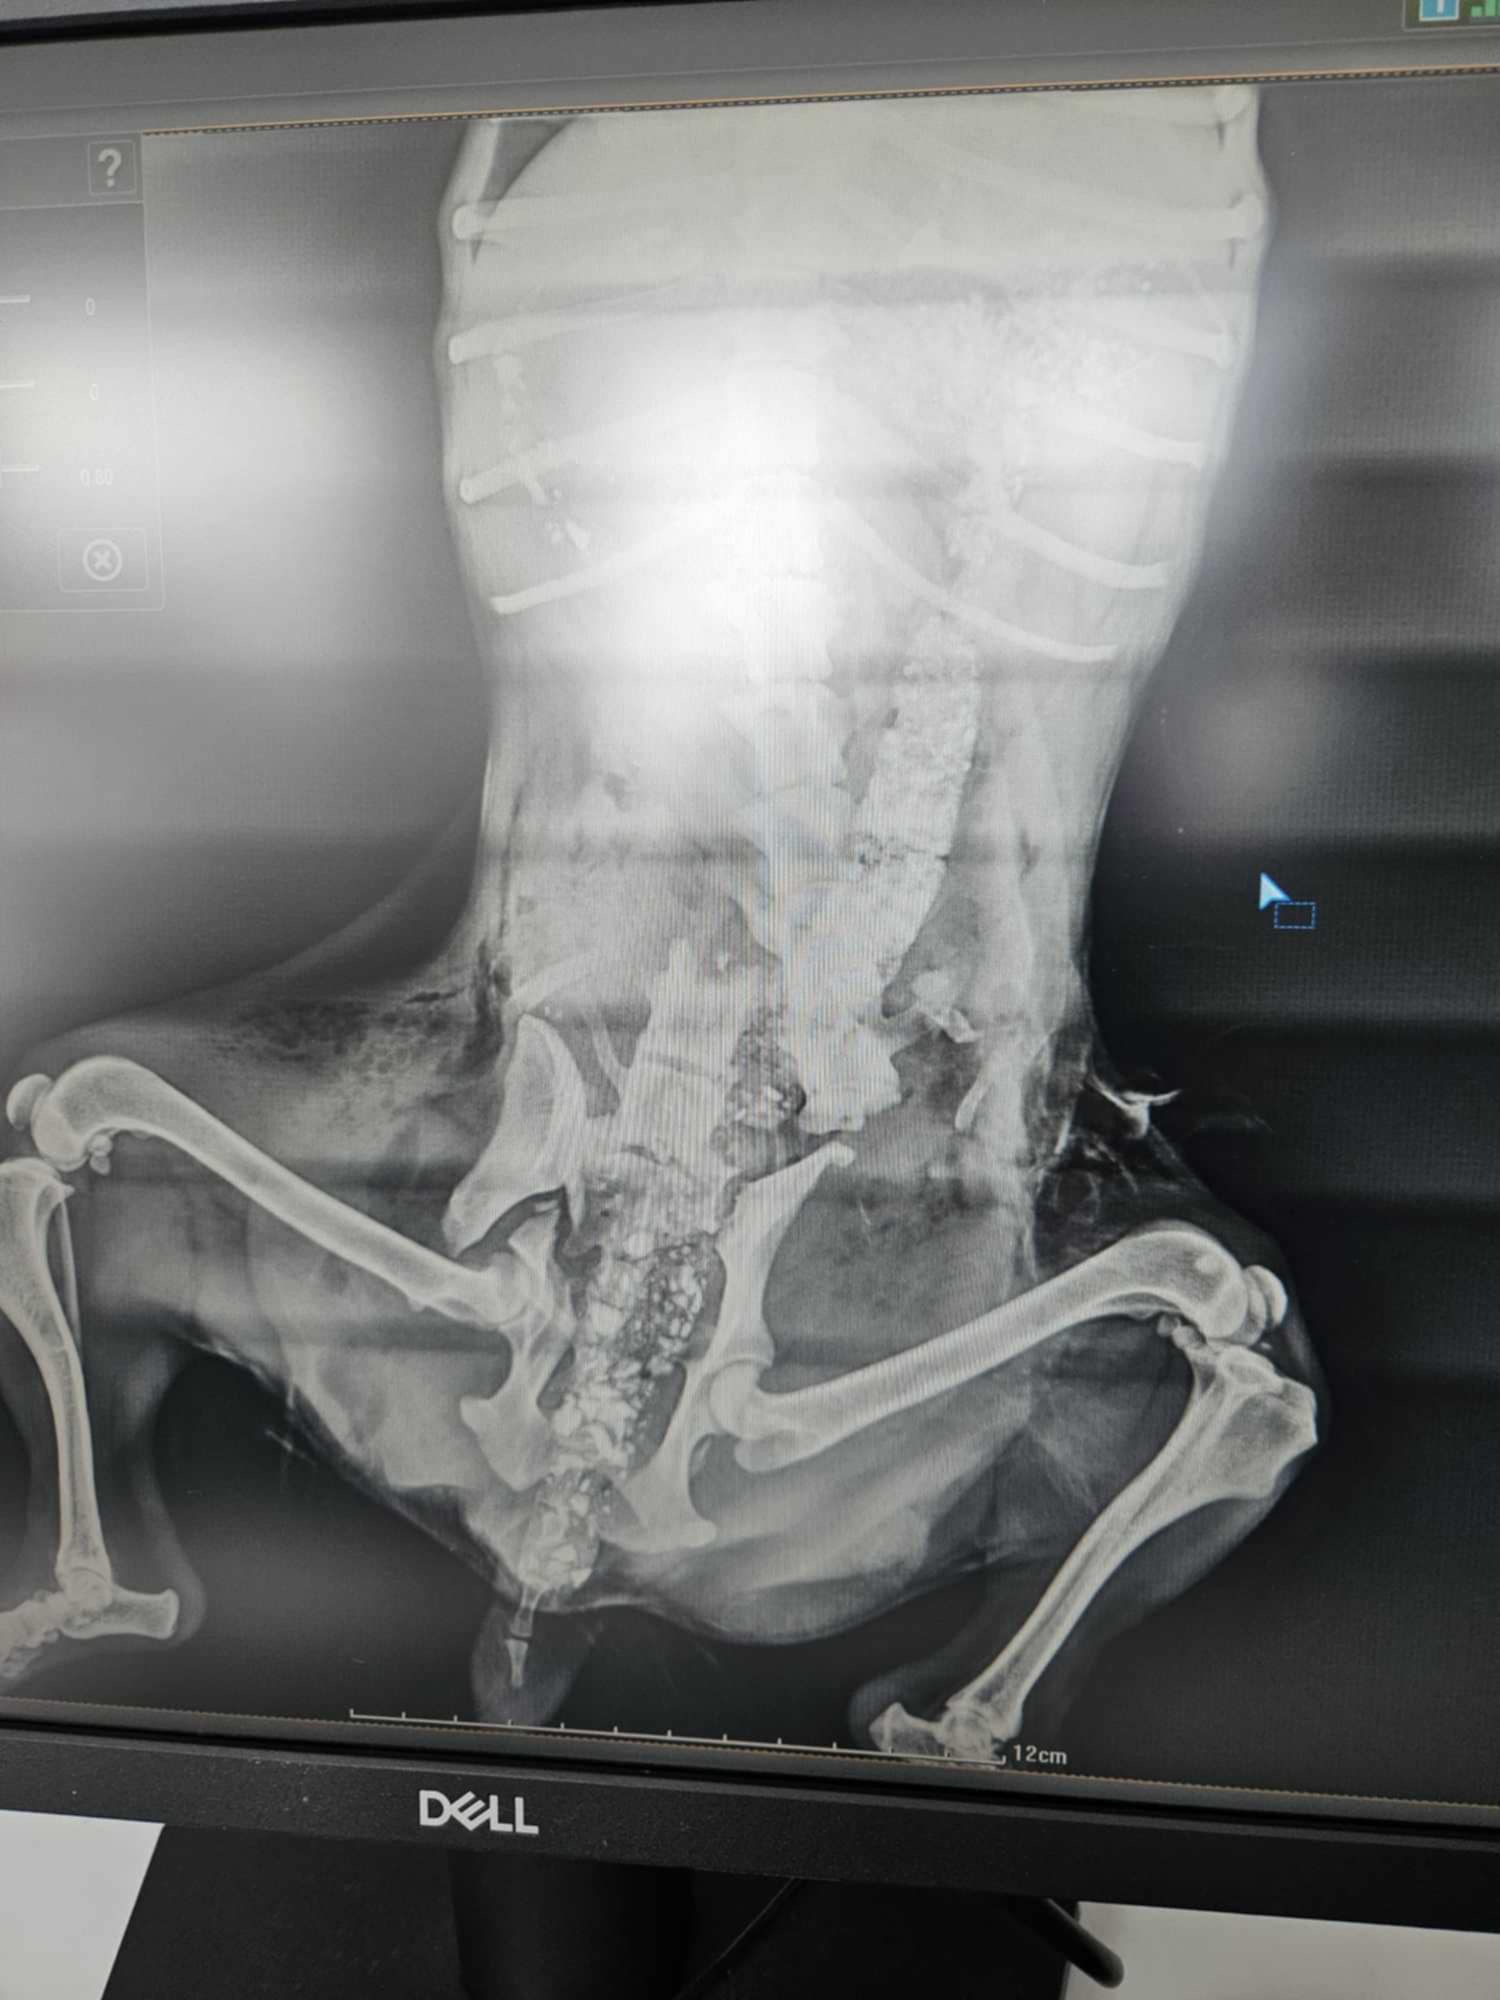

Dec 27, 2024Op 3 december 2024 werd een klein meisje gevonden. 4 kilo, verlamd. Ze was aangevallen door zwerfhonden en had haar ruggengraat en heupen gebroken. Het asiel STORGI ANIMAL WELFARE in Skydra, Griekenland, noemde haar Rapunzel. Bekijk hier haar reddingsverhaal. Het kleine meisje had pijn en was in shock, en depressief. Natuurlijk werd ze meteen naar de dierenarts gebracht en kreeg ze benchrust en natuurlijk medicatie voorgeschreven. In het begin wilde ze niet eten, maar na een paar dagen begon ze heel goed te eten.